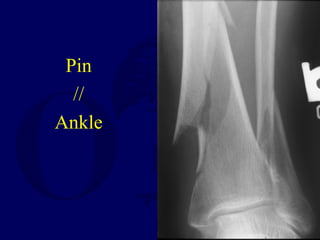

Nailing

Distal

Tibia

Reduction of Distal Tibial

Fractures

• Distractor

• Joy Stick

• Fibular Plating

• Calcaneal Traction

Pin

//

Ankle

Plate

Fibula

+ Alignment

- Dynamization

Proximal and Distal Cases Courtesy

of

R. Winquist M.D.